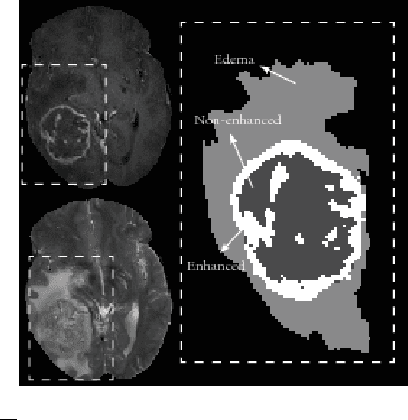

Abstract:Purpose: In this paper, we investigate a framework for interactive brain tumor segmentation which, at its core, treats the problem of interactive brain tumor segmentation as a machine learning problem. Methods: This method has an advantage over typical machine learning methods for this task where generalization is made across brains. The problem with these methods is that they need to deal with intensity bias correction and other MRI-specific noise. In this paper, we avoid these issues by approaching the problem as one of within brain generalization. Specifically, we propose a semi-automatic method that segments a brain tumor by training and generalizing within that brain only, based on some minimum user interaction. Conclusion: We investigate how adding spatial feature coordinates (i.e. $i$, $j$, $k$) to the intensity features can significantly improve the performance of different classification methods such as SVM, kNN and random forests. This would only be possible within an interactive framework. We also investigate the use of a more appropriate kernel and the adaptation of hyper-parameters specifically for each brain. Results: As a result of these experiments, we obtain an interactive method whose results reported on the MICCAI-BRATS 2013 dataset are the second most accurate compared to published methods, while using significantly less memory and processing power than most state-of-the-art methods.